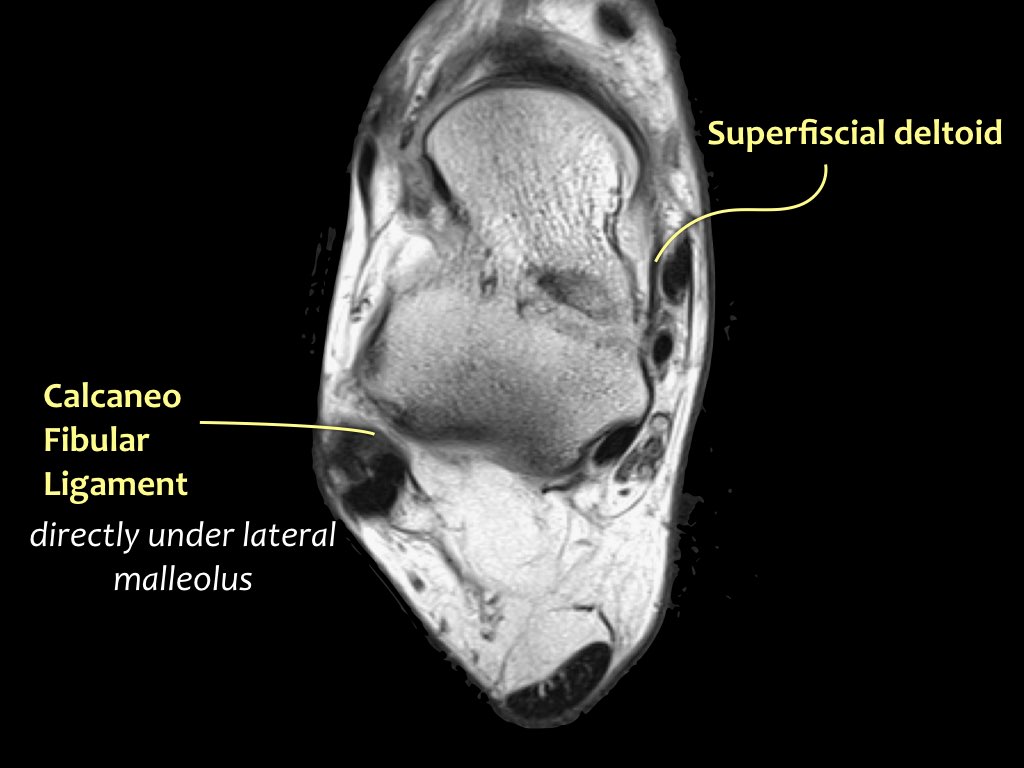

Có ba dây chằng ở phía ngoài:

- Dây chằng sên mác trước (anterior talofibular ligament – ATFL)

- Dây chằng gót mác (calcaneofibular ligament – CFL)

- Dây chằng sên mác sau (posterior talofibular ligament – PTFL).

Dây chằng ATFL chạy từ mắt cá ngoài ra phía trước đến bờ ngoài của xương sên.

Dây chằng này có hướng nằm ngang và được quan sát rõ nhất trên ảnh cắt ngang.

Đây là dây chằng bị tổn thương thường gặp nhất ở cổ chân và cũng là dây chằng đầu tiên bị tổn thương ở phía ngoài.

Điều này có nghĩa là khi dây chằng CFL hoặc PTFL bị tổn thương, rất có khả năng dây chằng ATFL cũng đã bị tổn thương.